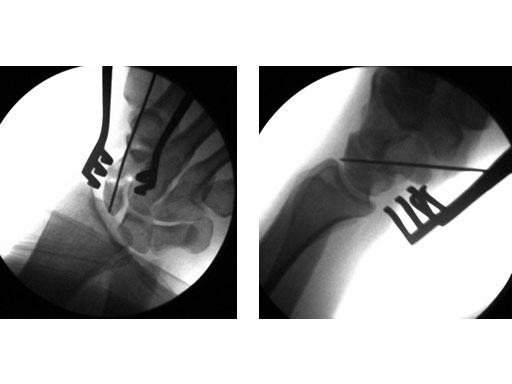

24-year-old male with an acute scaphoid wrist fracture treated by percutaneous fixation with a 3.0 mm headless compression screw under regional anesthesia.

Fig 2ab Intraoperative images.

Fig 3ab Postoperative images.